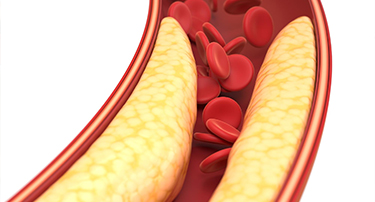

10 Natural Ways to Lower Cholesterol and Improve Heart Health

Although elevated cholesterol can cause health problems, it is necessary for several vital body processes. Exercise and dietary changes may help lower cholesterol, but some people will also require medication. All of the cholesterol required by the body is naturally produced by the liver. However, the liver can manufacture more cholesterol when some foods are consumed, while other foods include cholesterol. The National Heart, Lung, and Blood Institute states that the main cause of high cholesterol is unhealthy lifestyle choices. You can enhance the armada of fats in your bloodstream and reduce your bad cholesterol by making right dietary changes. The easiest strategy behind a low cholesterol diet is to include foods that reduce LDL, the dangerous cholesterol-carrying particle that causes artery-clogging atherosclerosis.

Good vs. Bad Cholesterol: What You Need To Know About HDL And LDL

Cholesterol is a vital substance in the body, yet its role is often misunderstood. While it is essential for building cells and producing hormones, an imbalance can lead to serious health issues. Understanding the difference between good and bad cholesterol—HDL and LDL—is crucial for maintaining heart health and overall well-being. This article delves into the types of cholesterol, their effects on the body, and how to manage them effectively.

How to Reduce Cholesterol by Food: Cholesterol Reducing Foods

Cholesterol is a type of fat that is produced by the liver and also absorbed from the foods we eat.Cholesterol plays a crucial role in forming cell membranes and producing hormones, essential for various bodily functions.However, an imbalance in cholesterol, especially with high levels of LDL (low-density lipoprotein), can lead to serious health risks, such as heart disease, stroke, and other cardiovascular issues.